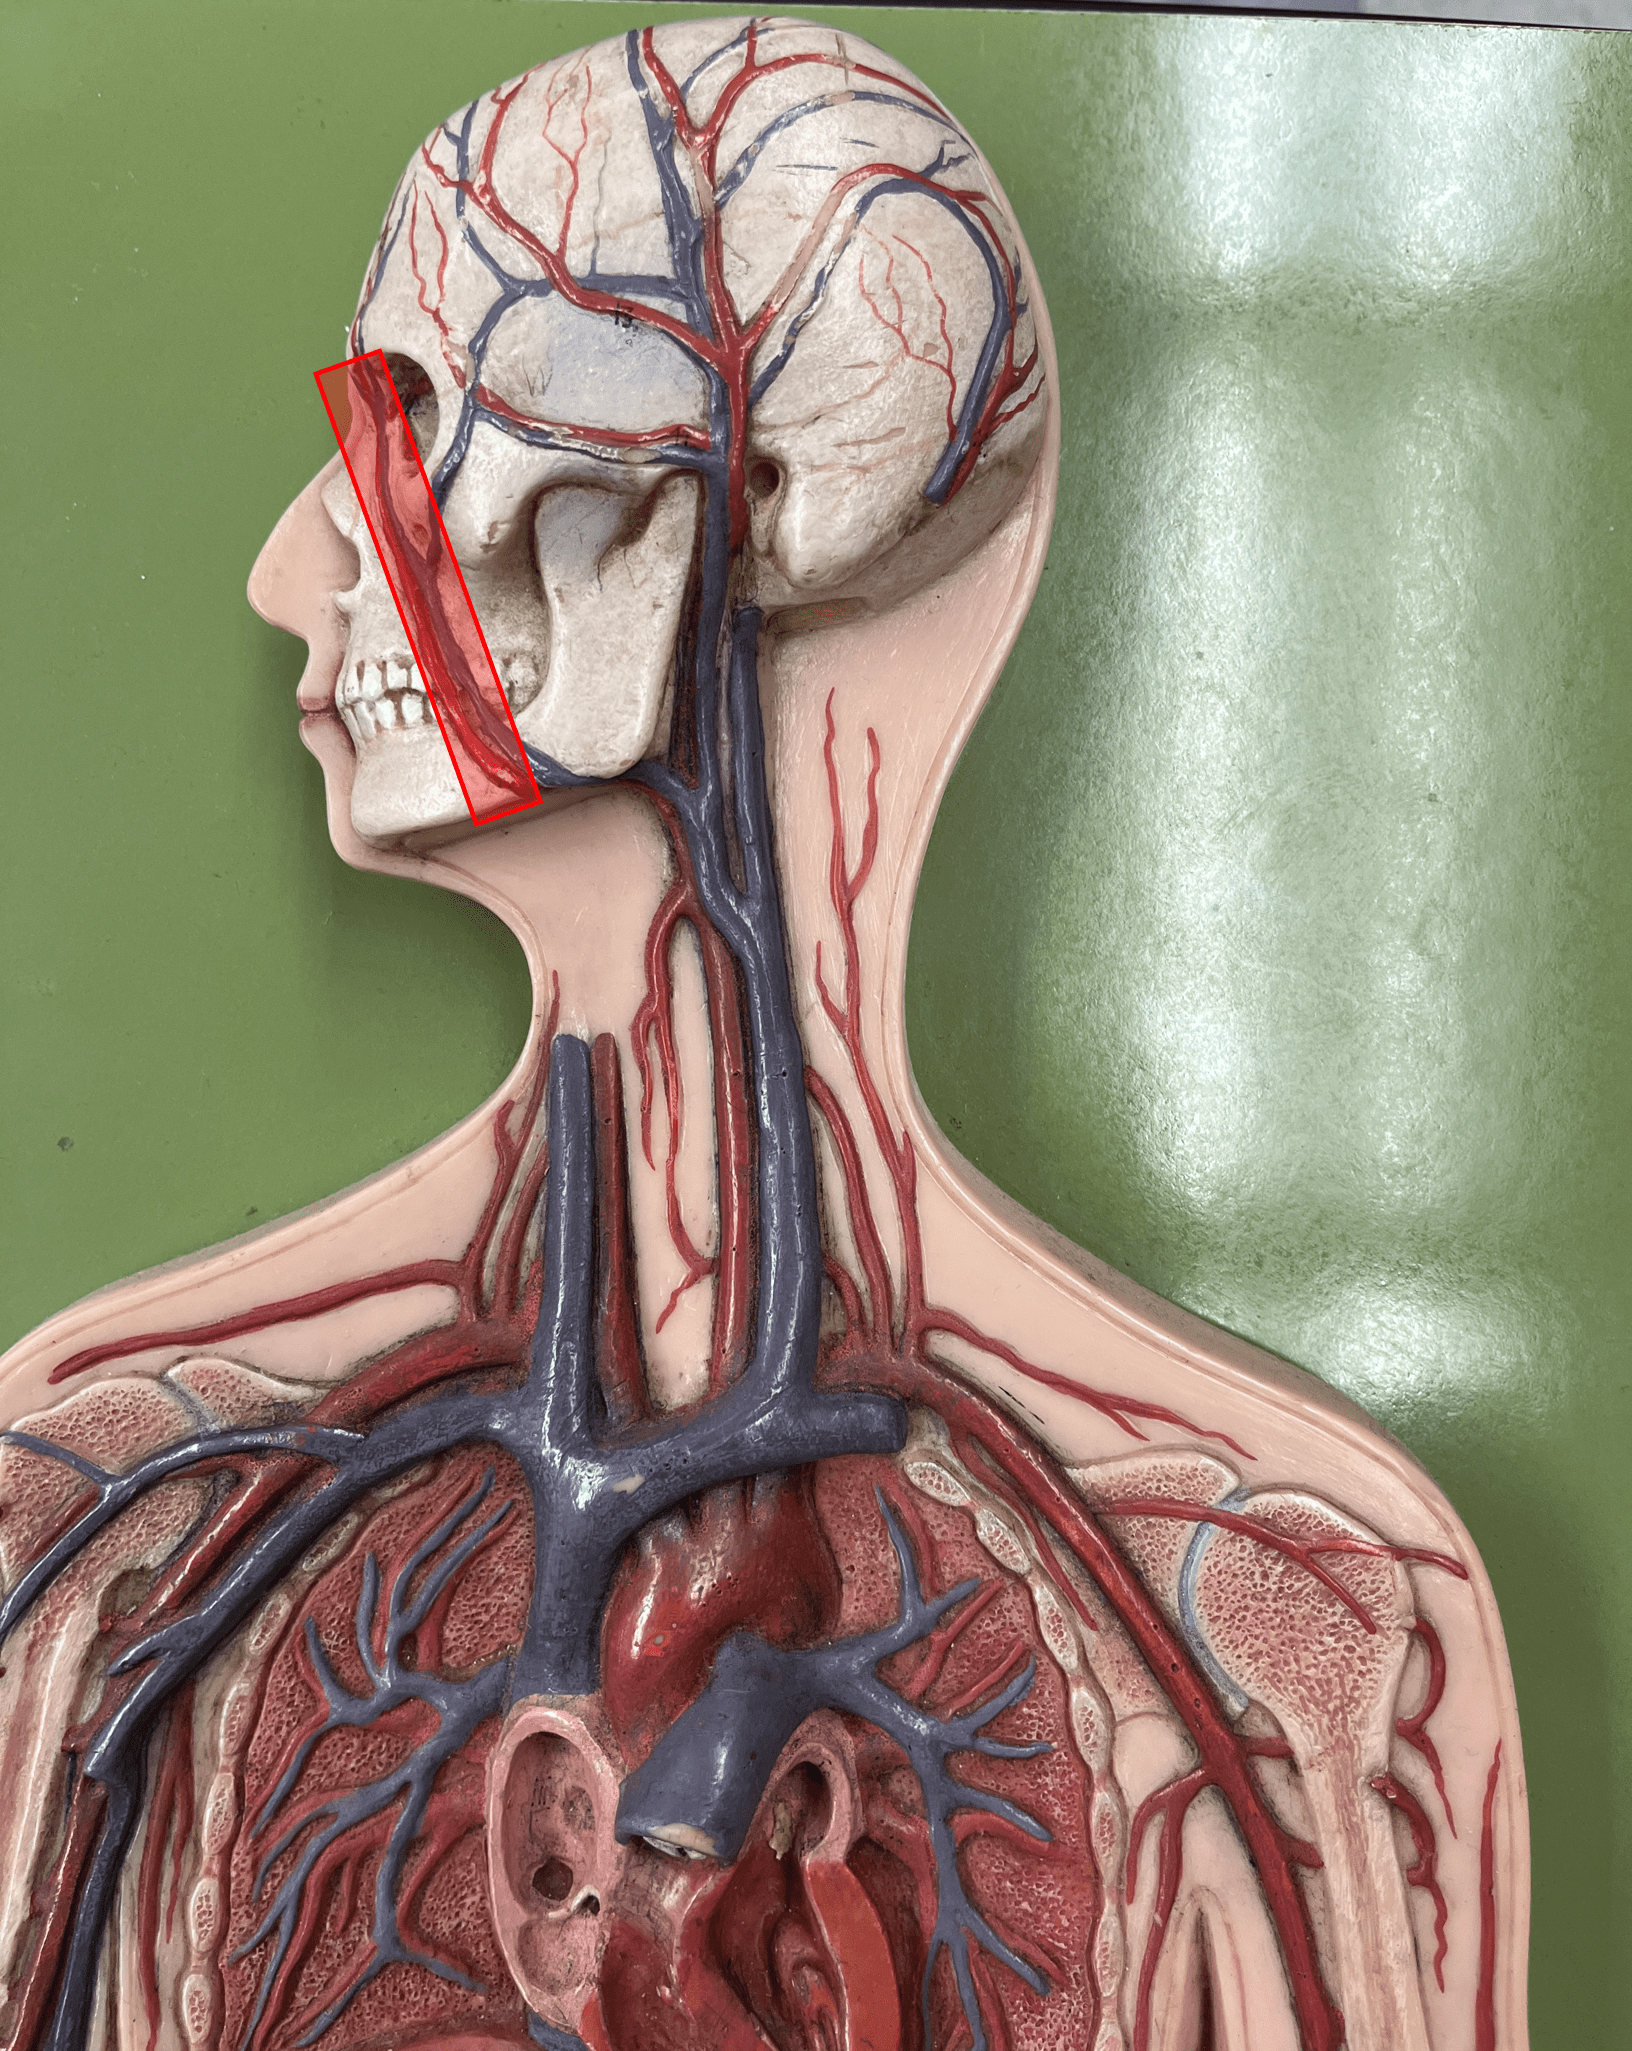

facial artery

• An artery of the head and neck.

• Originates from the external carotid artery.

• Supplies the skin and muscles of the face.

• Originates from the external carotid artery.

• Supplies the skin and muscles of the face.